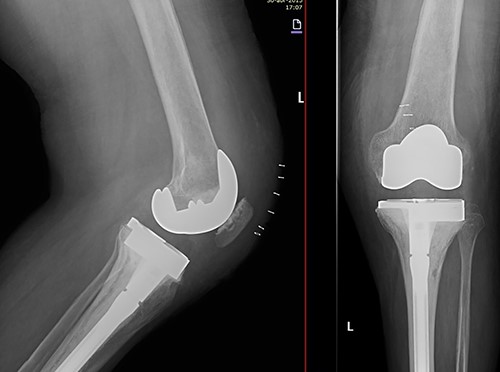

She was referred to our Service to evaluate progressive and disabling pain in both knees. Physical examination revealed bilateral quadriceps atrophy with valgus laxity in the left knee and varus laxity in her right knee. Range of motion (ROM) in both knees was 0°–100°. Standing radiographs showed a pattern of diffuse osteopenia and necrosis (Fig. 1).

Initial both-legs standing radiographs of the knee. It showed a pattern of diffuse osteopenia with areas of sclerosis, lateral extended bone reaction and decreased lateral articular space (Kellgren–Lawrence 3) in the left knee. Bone necrosis with decreased medial articular space (Kellgren–Lawrence 3) were observed in the right knee.